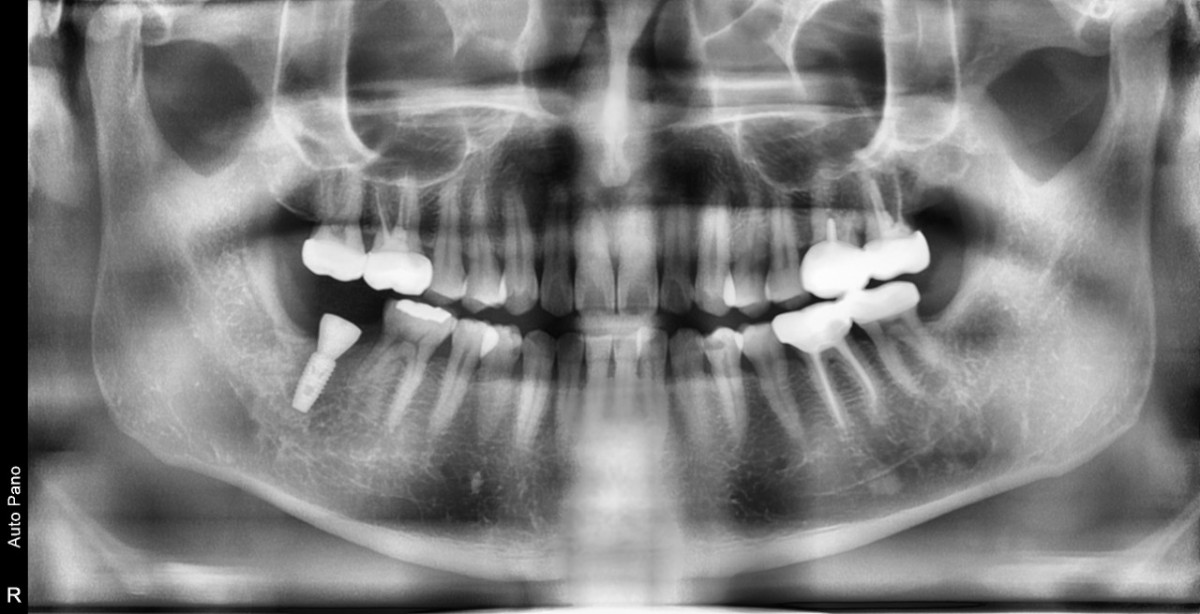

Single implant (staged) Arum NB1, f/u

A 47-year-old male patient had a crown with an ill-fitting margin and crack-tooth syndrome in the lower 2nd molar. No systemic issue.